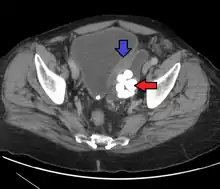

• Urethral diverticula are usually found in women aged 30 to 70 years old, in between 1 and 6% of adult women. Since most cases are without any symptoms, the true incidence is unknown. Symptoms may vary from frequent urinary tract infections, painful sexual intercourse (dyspareunia), or symptoms due to cancer. A urethral diverticulum is located on the anterior vaginal wall, 1 to 3 cm inside the vaginal introitus. MRI is preferred as the imaging method of choice due to its excellent soft-tissue resolution. On T2-weighted imaging, it shows a high signal in the diverticulum due to the presence of fluid inside it. Vaginal ultrasonography is highly sensitive in diagnosing the diverticulum, but it is strongly dependent on the skills of the operator.[15]